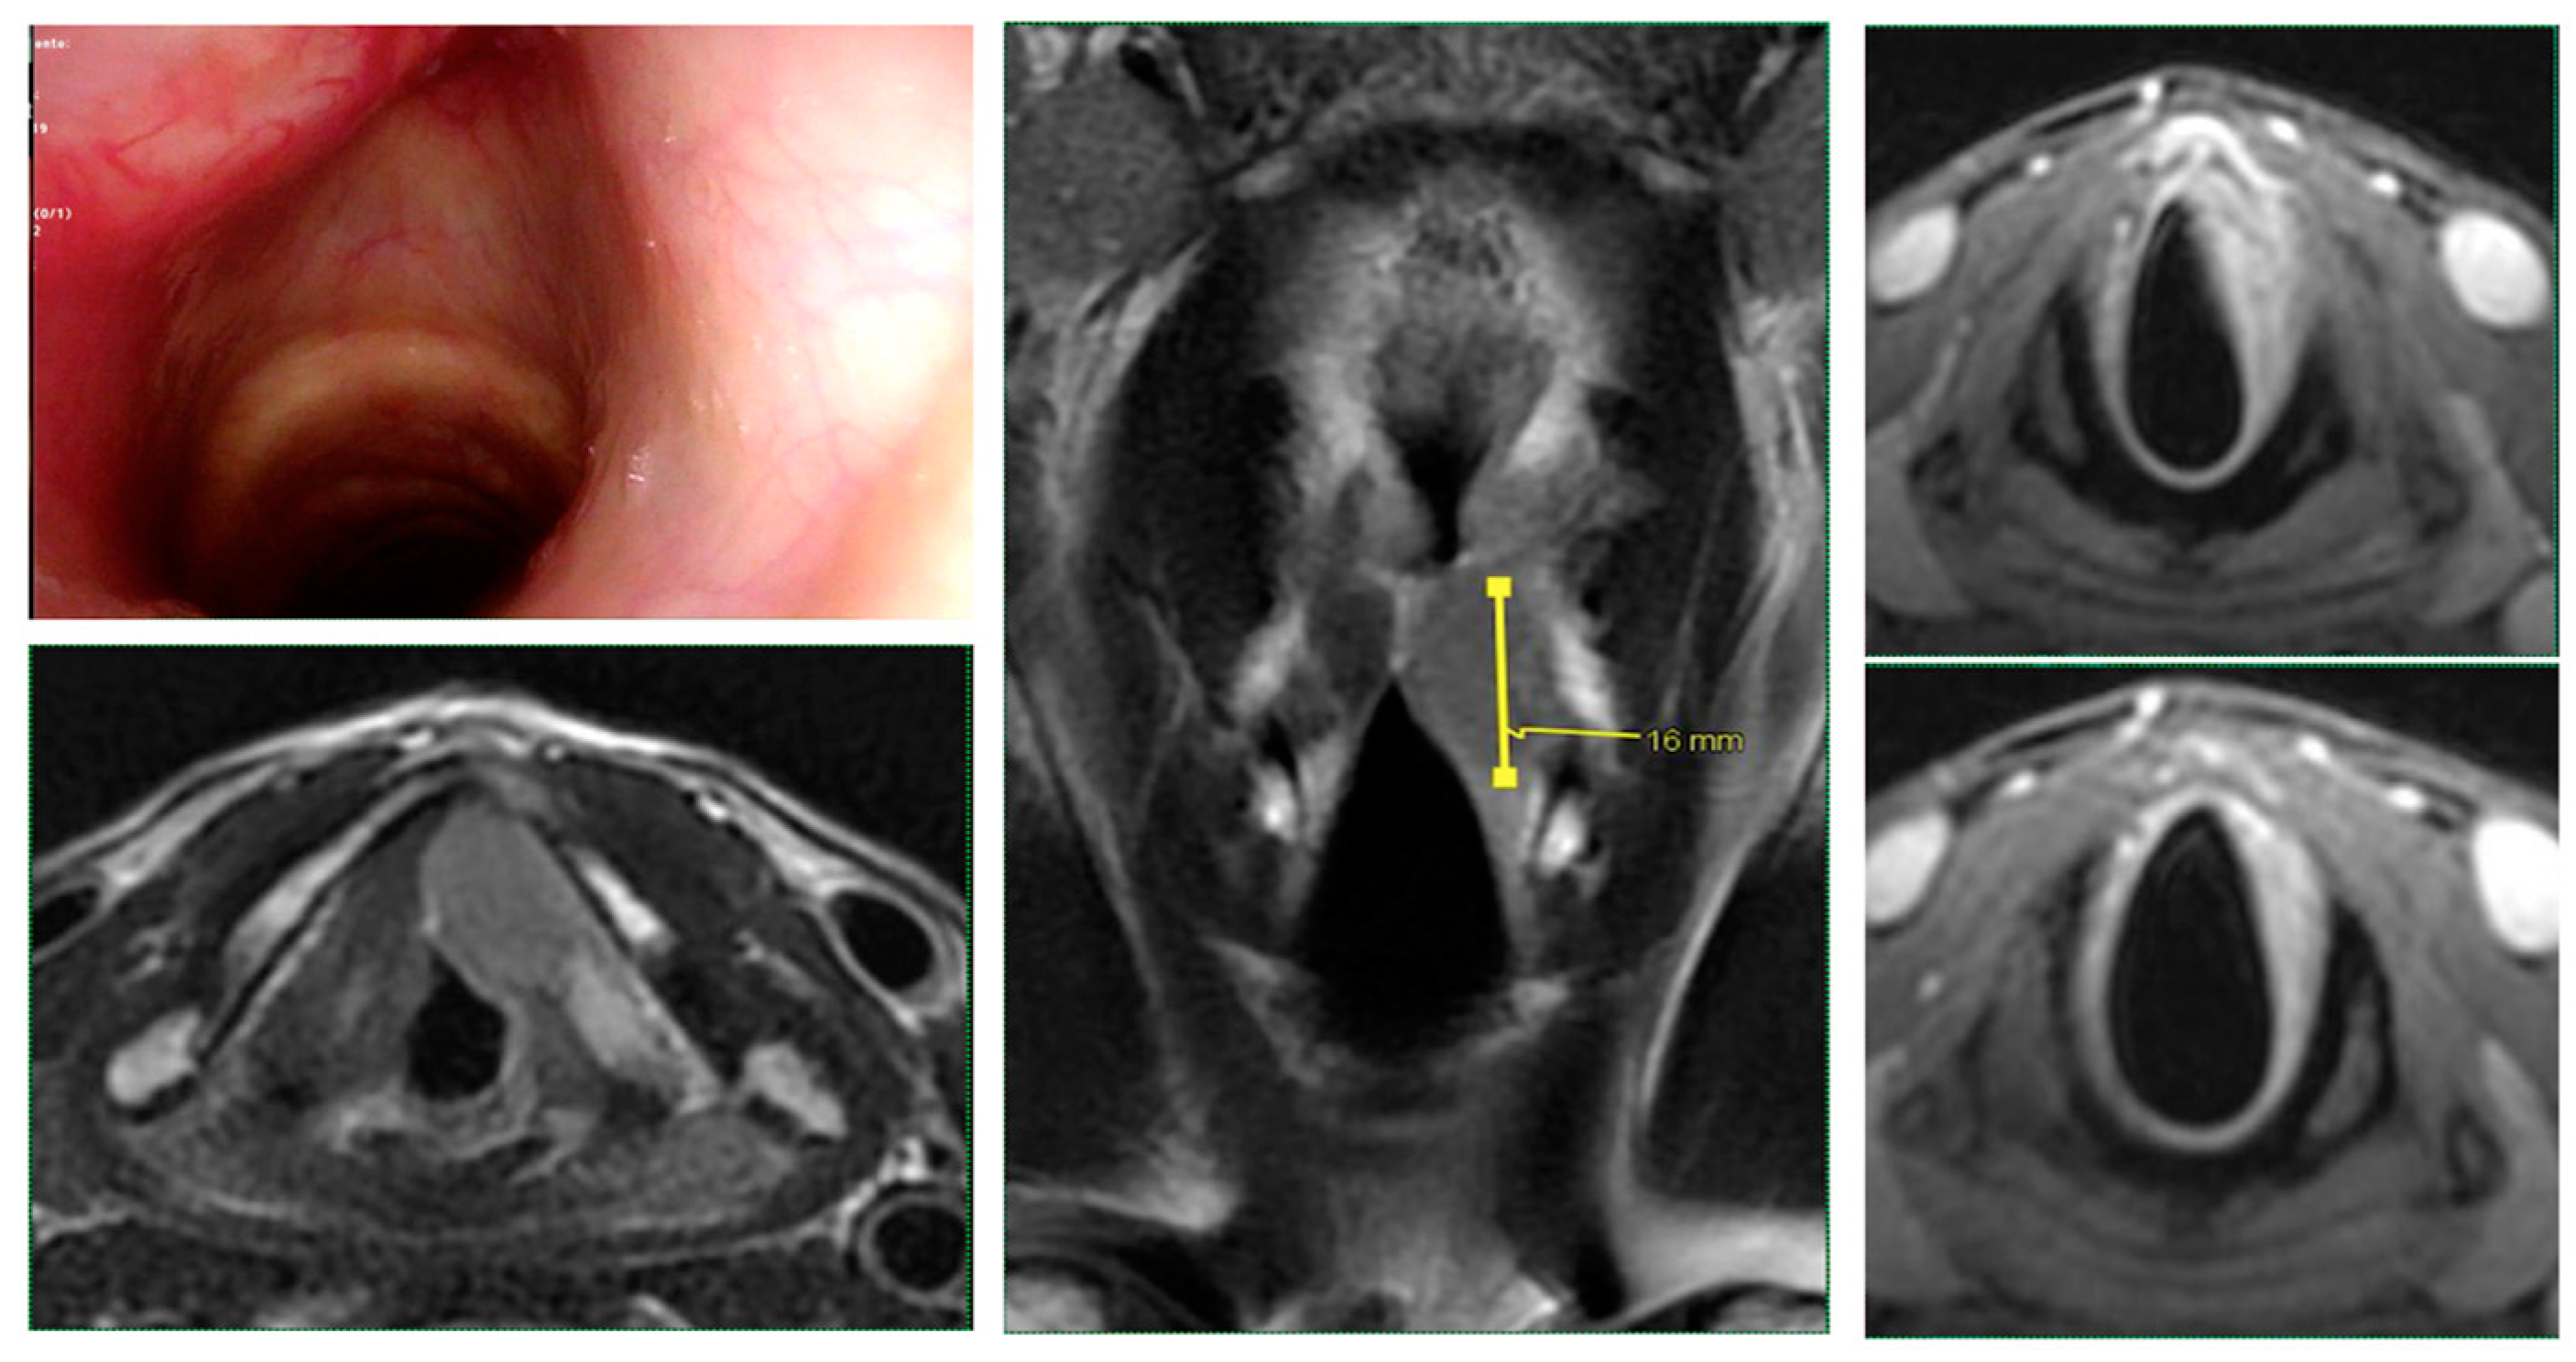

Intraoperative endoscopy allowed for a thorough reassessment of the tumor extension and highlighted some clinical-endoscopic elements of suspected initial extra laryngeal extension (Figure 1 and Figure 2).

Figure 1. Glottic squamous cell carcinoma cT3 (left vocal cord): endoscopic and radiological (MRI) picture: the tumor was likely to be sub-staged with endoscopic evaluation alone.